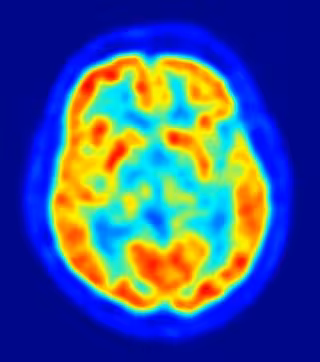

Un equipo de científicos ha descubierto una mutación, limitada al tejido cerebral, que causa hemimegalencefalia (HMG), una condición en la que una mitad del cerebro se agranda, y se vuelve disfuncional -causando discapacidad intelectual y epilepsia severa. La investigación, publicada en la revista 'Neuron', sirve de modelo potencial para otras enfermedades neuropsiquiátricas complejas, que también pueden ser causadas ??por mutaciones en el cerebro.

"La sorprendente asimetría del cerebro, en las personas con HMG, ya indicaba que esta enfermedad puede ser causada por una mutación espontánea restringida a la mitad del cerebro, y detectable por estudio directo del tejido cerebral afectado", explica la primera autora del estudio, la doctora Ann Poduri, del Hospital Infantil de Boston, y la Escuela Médica de Harvard, en EE.UU.

Los pacientes con HMG suelen sufrir decenas de ataques por día, lo cual perturba su desarrollo cognitivo, y lleva a los médicos a tomar la difícil decisión de eliminar tejido cerebral, en un intento desesperado por controlar las convulsiones. Afortunadamente, estas operaciones, con frecuencia, tienen éxito en el control de las crisis, y permiten que los niños afectados se desarrollen con normalidad. A partir del tejido cerebral proporcionado por estas operaciones. Poduri y sus colaboradores identificaron mutaciones en el gen AKT3 del tejido cerebral con HMG.

"Nuestros datos sugieren que las mutaciones espontáneas, resultantes de la activación anormal de AKT3, contribuyen al crecimiento excesivo de la mitad del cerebro. El tamaño y la arquitectura de HMG pueden ser determinados, en parte, por la etapa en que la mutación se produce, en relación con la etapa de desarrollo del cerebro ", concluye el coautor del estudio, el doctor Christopher Walsh, del Hospital Infantil de Boston, el Instituto Médico Howard Hughes, y la Escuela de Medicina de Harvard. Walsh añade que, "esta la primera enfermedad atribuida a mutaciones limitadas al tejido cerebral. Por lo tanto, otras epilepsias y enfermedades neuropsiquiátricas, asociadas a mutaciones espontáneas, también pueden ser el resultado de este tipo de mutaciones".